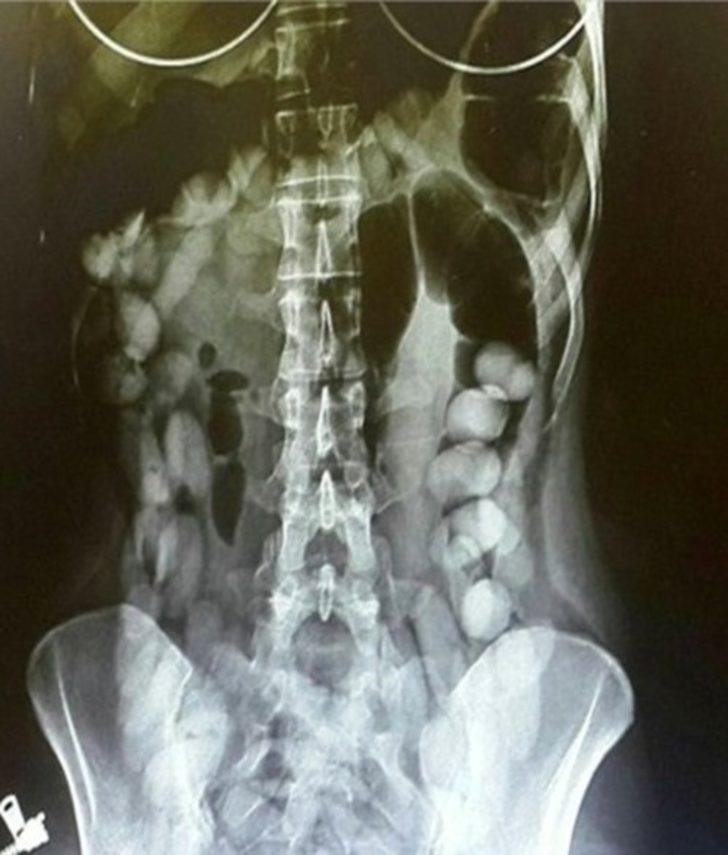

RÖNTGEN ÇEKİLİNCE ORTAYA ÇIKTI

O.R. isimli yabancı uyruklu şahsın şeffaf poşetlere sararak yuttuğu 5 poşet halindeki uyuşturucu maddeler adli makamlarca yaptırılan sağlık kontrollerinde radyoloji çekimiyle görüntülendi. Hastanedeki tıbbi müdahale ile şahsın yuttuğu 2,5 gram eroin maddesi çıkartıldı. Mahkemeye sevk edilen şüpheli tutuklandı.